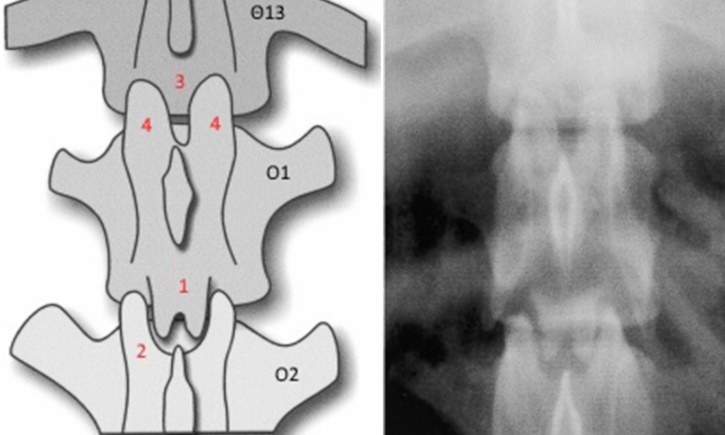

Kοιλιοραχιαία θωρακοσφυϊκή ακτινογραφία και σχεδιάγραμμά της θωρακοσφυϊκής μοίρας της ΣΣ.

Η αποφυσιακή άρθρωση μεταξύ Ο1-Ο2 είναι φυσιολογική αποτελούμενη από τις οπίσθιες αρθρικές αποφύσεις του Ο1, που δημιουργούν ένα σχήμα «διπλής κυρτότητας ή καμπούρας» (1) και τις πρόσθιες αρθρικές αποφύσεις του Ο2 (2), που δημιουργούν κοιλότητα στην οποία προσαρμόζονται οι οπίσθιες αρθρικές αποφύσεις του Ο1. Οι οπίσθιες αρθρικές αποφύσεις του Θ13 απουσιάζουν (3) και οι πρόσθιες αρθρικές αποφύσεις του Ο1 είναι παχυμένες και φέρονται προς τα μέσα.